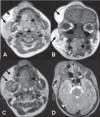

Congenital infiltrating lipomatosis of the face is a rare condition characterized by diffuse fatty infiltration of the facial soft tissues. There may be muscle involvement along with associated bony hyperplasia. It is a type of lipomatous tumor that is congenital in origin; it is rare and seen usually in childhood. We recently saw an 11-year-old girl with this condition. She presented with a swelling of the right side of the face that had been present since birth; there were typical findings on plain radiographs, CT, and MRI. The patient underwent cosmetic surgery. Histopathological examination showed mature adipocytes without any capsule.